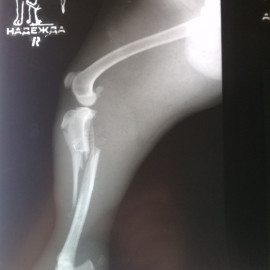

Ветеринарная клиника "Надежда" использует при проведении ортопедических операций компрессионно-дистракционный аппарат Илизарова.

Наш пациент успешно прошел курс реабилитации и быстро начал пользоваться конечностью.